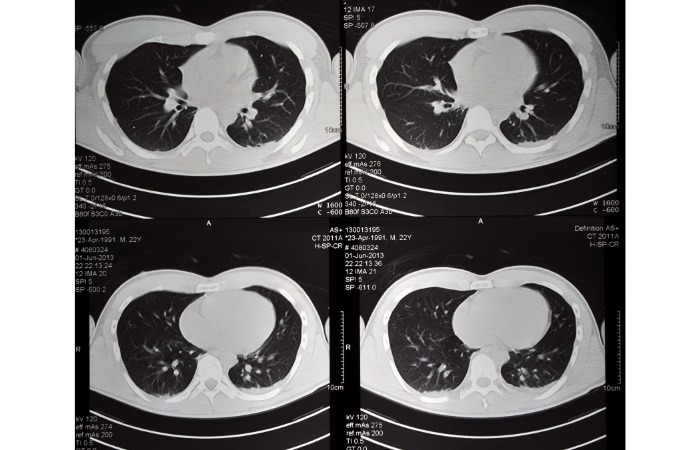

توزیع پرتودهی در سی تی اسکن سر و قفسه صدری

تحلیل علمی توزیع پرتودهی در سی تی اسکن سر و قفسه صدری به عنوان یکی از حیاتی ترین مباحث فیزیک تصویربرداری پزشکی، نقش تعیین کننده ای در بهینه سازی دوز دریافتی بیمار و ارتقای کیفیت تصاویر ایفا می کند. در سیستم های نوین تصویربرداری، درک نحوه برهمکنش فوتون های ایکس با بافت های متراکم جمجمه […]